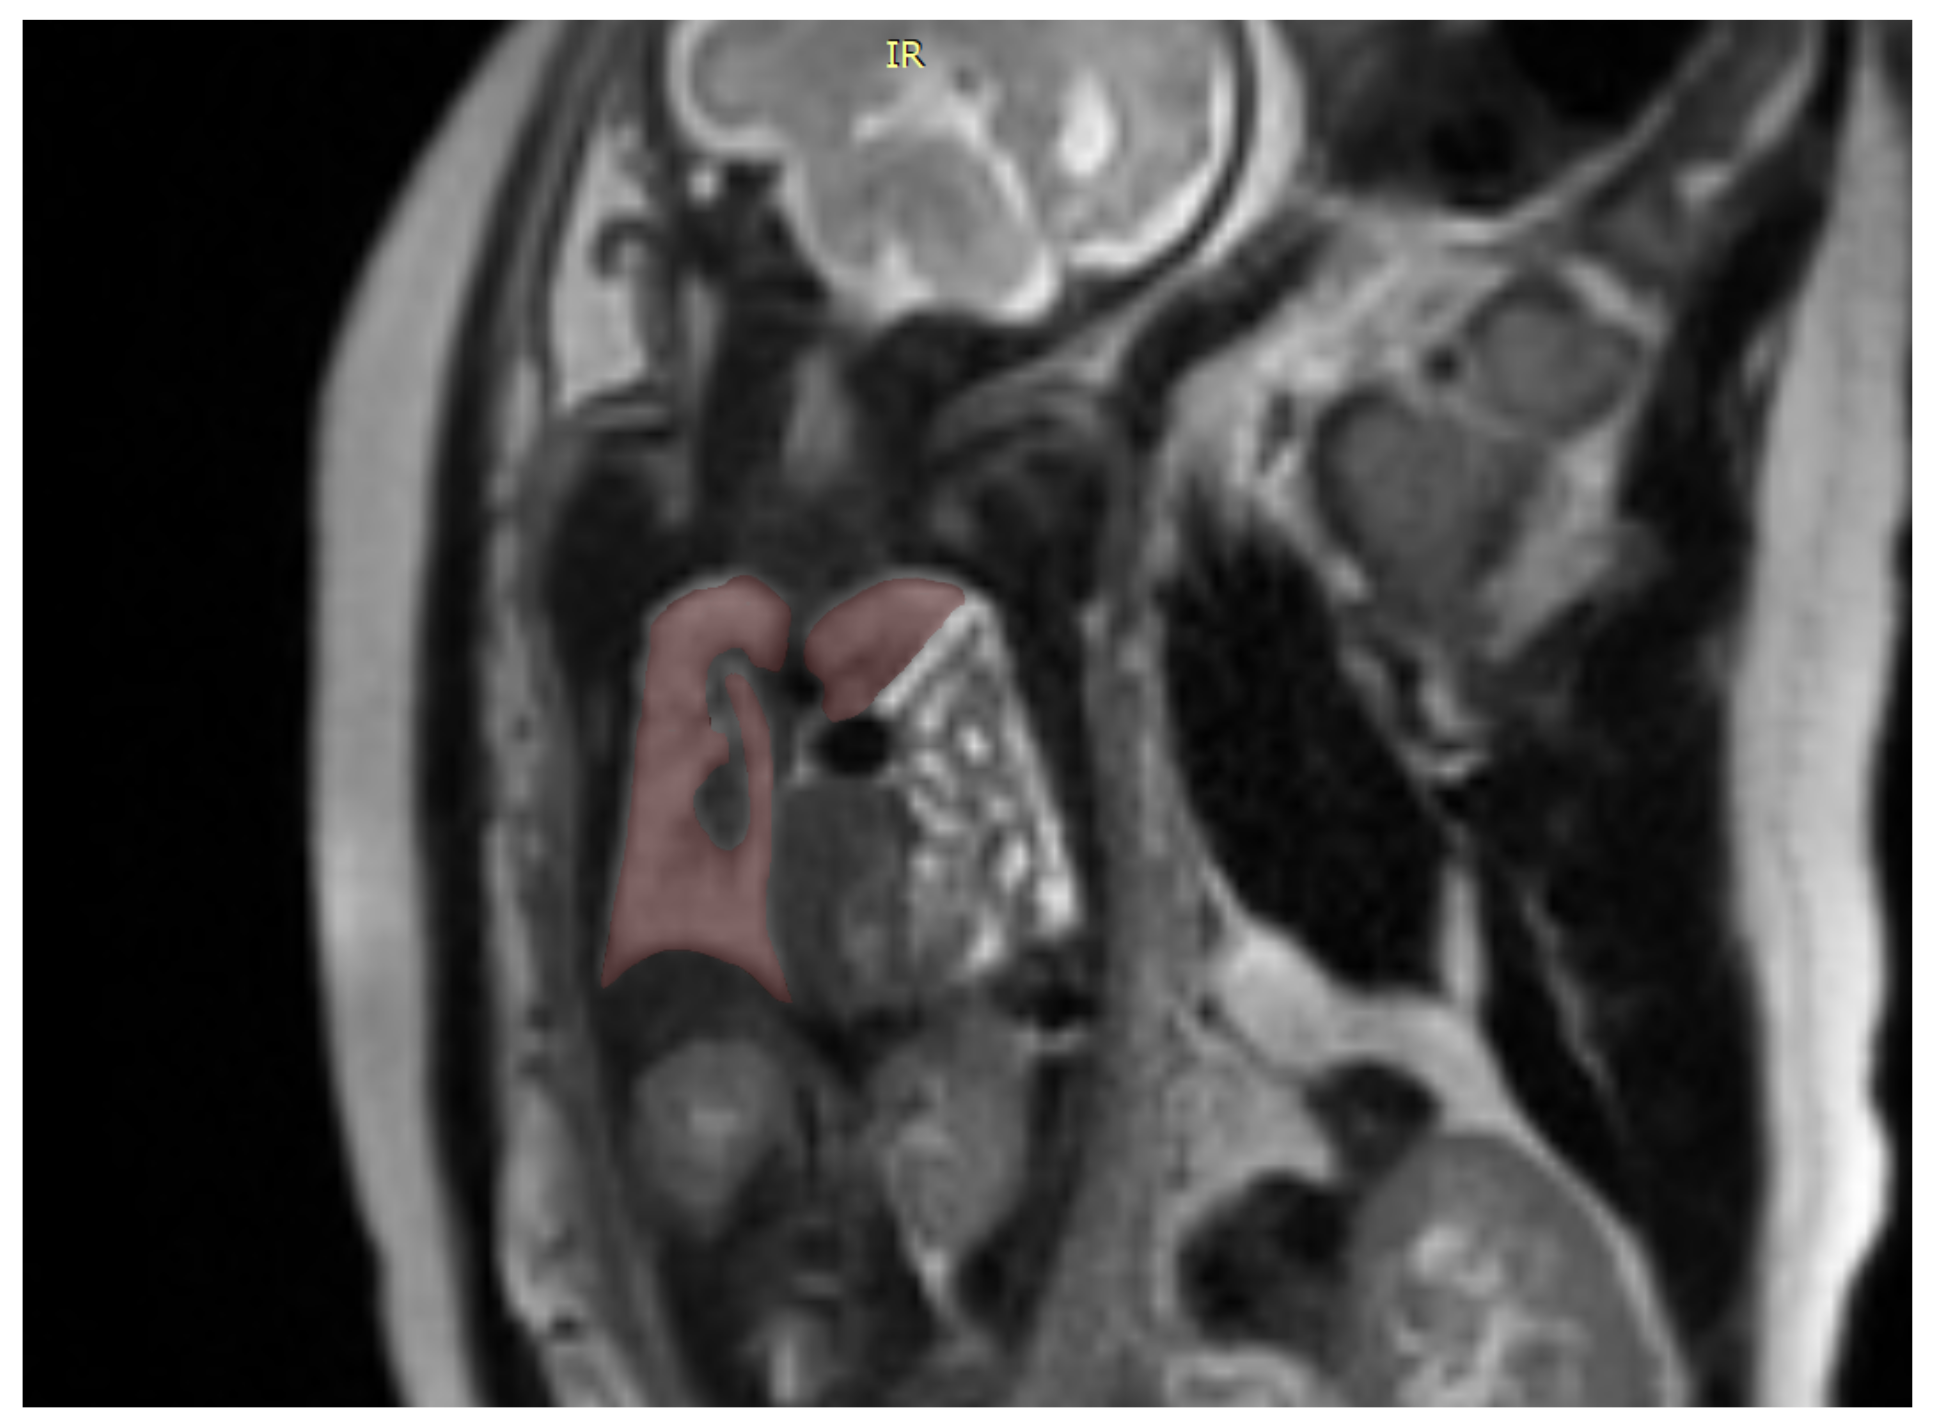

We also used a freeware program to obtain a 3D rendering of the lungs so that the modified anatomy might be better-visualized [17]. Figure 2.

ITK-SNAP is a software application used to segment structures in 3D medical images and is a general-purpose interactive tool for image visualization, manual segmentation, and semi-automatic segmentation Figure 3.

Figure 2. Coronal image of the fetus showing the tracing method for calculating the lung volume, using the ITK-SNAP program.

Figure 3. Showing a 3D rendition of the fetal lungs in Figure 1 and Figure 2 using the ITK-SNAP software.